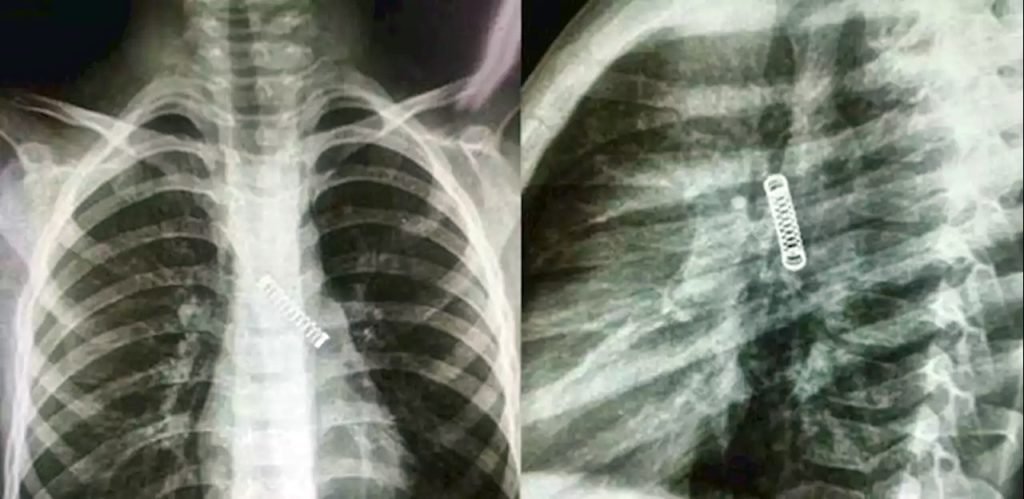

Um menino de 5 anos teve uma mola de metal removida de seu pulmão, depois do objeto ficar preso lá por três meses. O paraguaio de cinco anos sofria de uma tosse constante.

O menino foi submetido a um raio-X e os médicos ficaram surpresos ao encontrar um objeto de metal em seu pulmão esquerdo.